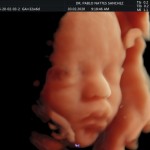

Modalidad de imagen ecográfica que permite evaluar, medir y capturar estructuras fetales superficiales e internas en 3 dimensiones (3D) y también en movimiento y en tiempo real (4D) con programas de realismo aumentado (HD LIVE) e imágenes tomografías fetales (TUI) mejorando significativamente la precisión en las mediciones fetales y la documentaciones de estructuras anatómicas.

Esta tecnología se puede utilizar desde la 6ta a la 40ma semana de embarazo.